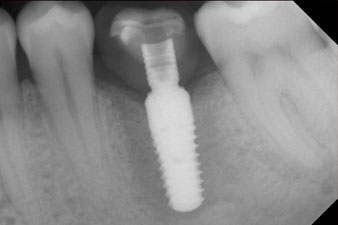

Después de la cicatrización de los tejidos blandos, se volvió a determinar la estabilidad del implante antes de continuar con el tratamiento protésico.

Los dos valores eran prácticamente idénticos y se encontraban en la transición del área media a la alta; en este punto cabe reseñar que el valor más bajo sirve siempre como referencia para establecer el tratamiento adecuado.

Con ello, fue posible documentar una correcta osteointegración y una estabilidad biológica suficiente, lo que permitió realizar una conformación en la misma sesión.